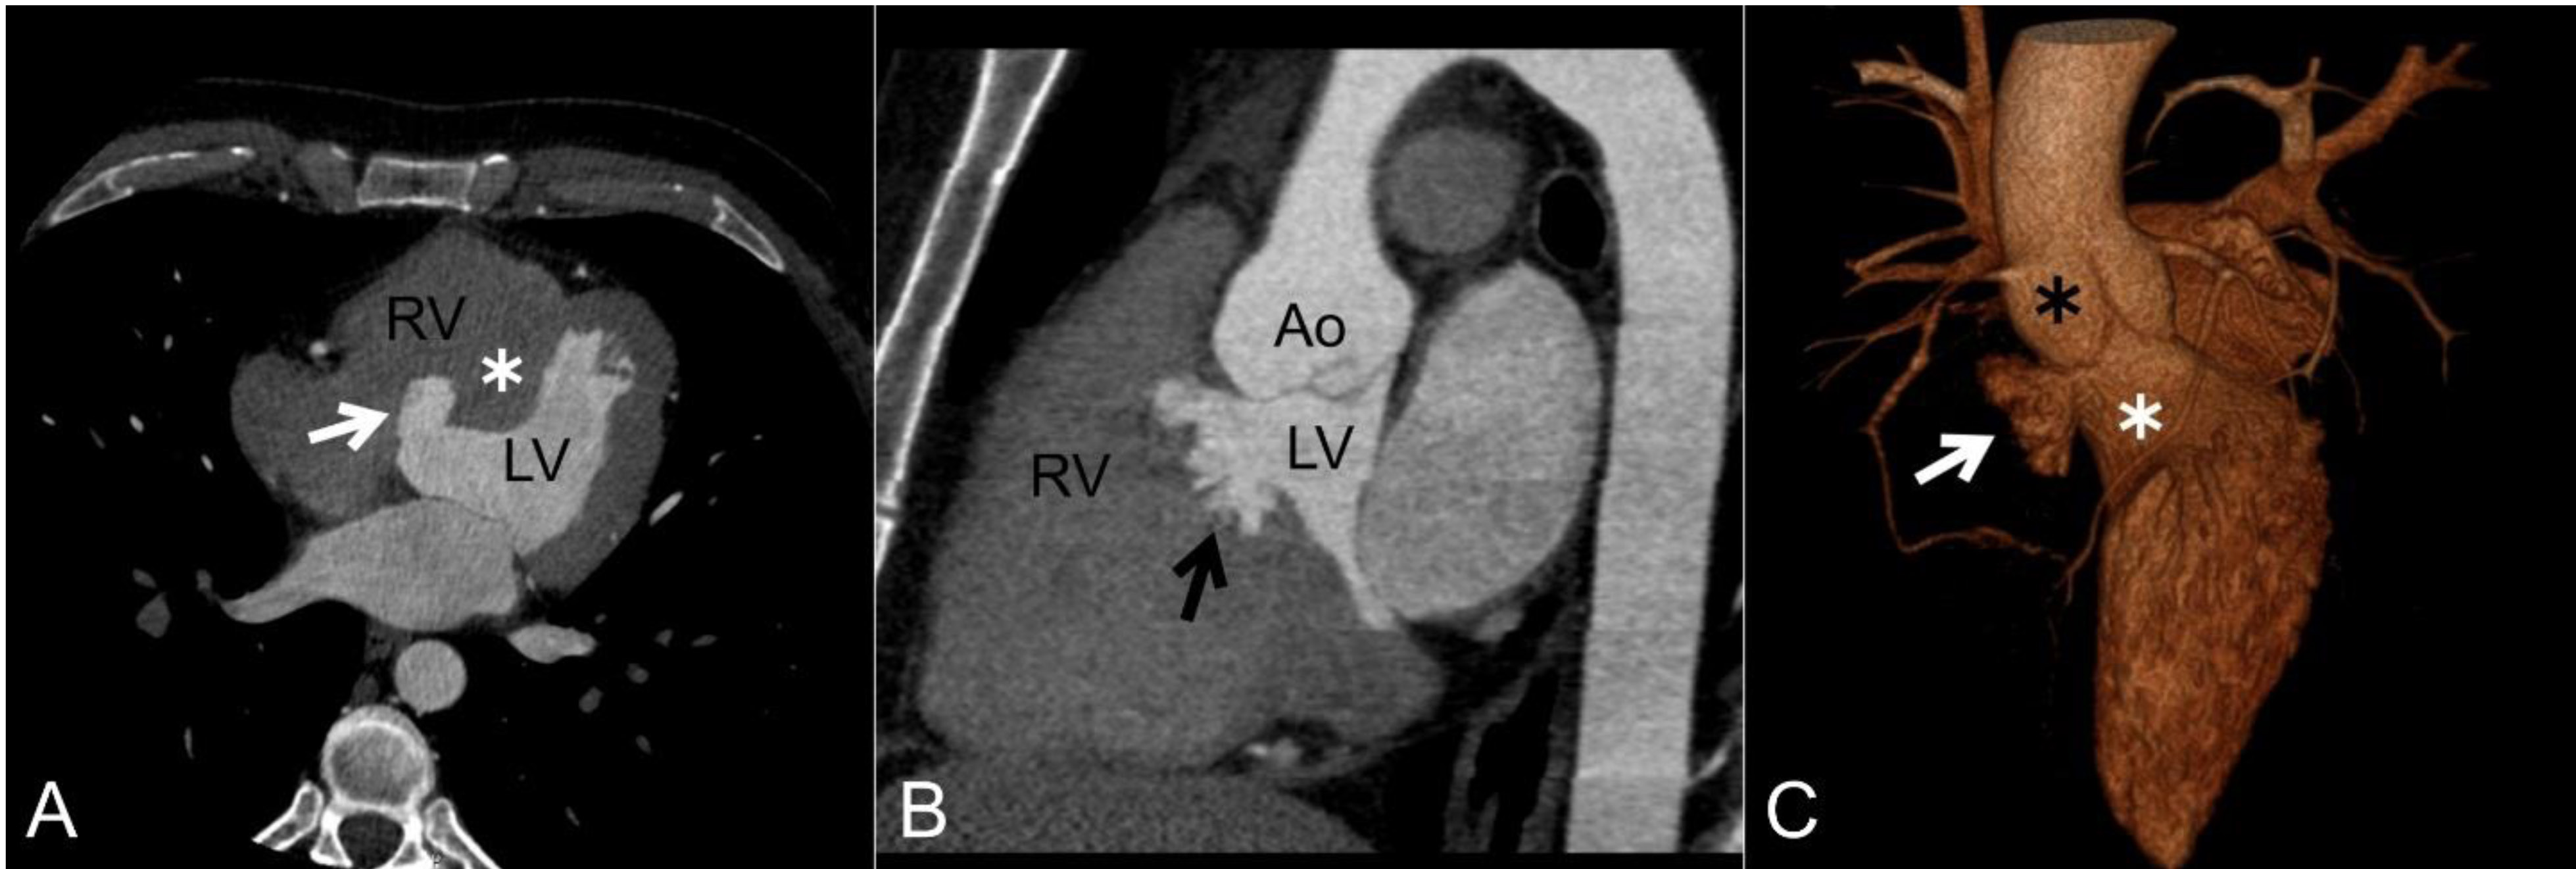

16.Free floating mitral paravalvular leak closure device

Aycan Esen Zencirci

doi: 10.5152/AnatolJCardiol.2021.1128  Page E3